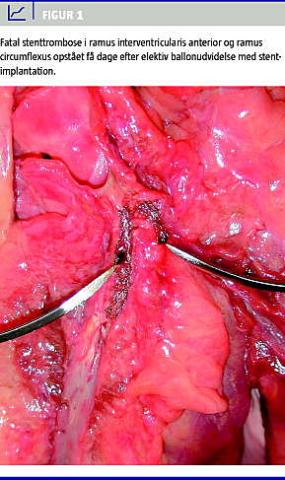

Koronare stents er intrakoronare fremmedlegemer, og de er derfor som udgangspunkt trombogene (Figur 1 ). Med henblik på at reducere forekomsten af stenttrombose anbefales dobbelt pladehæmmerbehandling med acetylsalicylsyre (ASA) livslangt og CLO (ofte i op til 12 måneder) efter PCI [1]. Samtidig behandling med PPI anbefales til patienter med øget risiko for øvre gastrointestinal blødning [2].